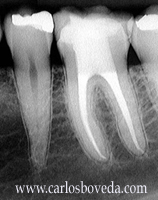

Video de un Tratamiento de Conductos en Una Sesión - (formato Quicktime)